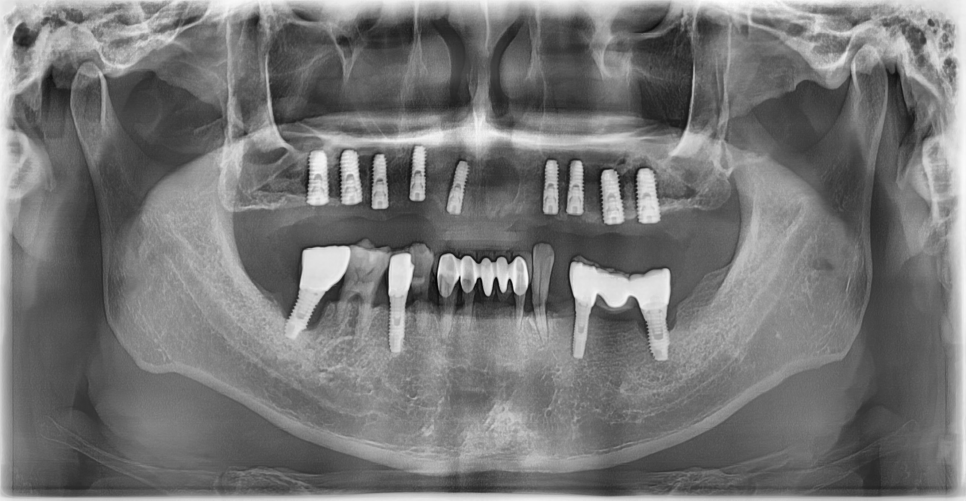

231122

이 환자분도 사진을 찍어보니

뼈가 많이 얇아져 있었습니다.

사진상에서 보면 이 부위가 상악동인데,

까맣게 보이는 이유는 안이 뻥~ 뚫려 있기 때문이죠.

임플란트를 안정적으로 심으려면

뼈의 높이가 최소 7~8mm는 되어야 합니다.

그런데 이 환자분은 1.5mm밖에 남지 않은 상태였습니다.

이 환자분은 위쪽 치아가 아예 없어서

총 9개의 임플란트를 심기로 계획했습니다.

양측 어금니 부분은 뼈가 얇아서

상악동 거상술과 뼈이식을 함께 진행하기로 했습니다.

CT도 같이 살펴볼게요.

노란색으로 표시한 잇몸뼈 부분,

눈으로 보기에도 굉장히 얇죠?

이렇게 상악동 안을 뼈로 채워 올릴 예정입니다.

식립 후 사진입니다.

231129

식립 전에는 이 하얀 부분인 뼈가 굉장히 얇았는데,

식립 후에는 이 하얀 부분이 더 많아진 것을 볼 수 있어요.

이 하얀 부분이 바로 뼈이식을 한 부위입니다.

임플란트 식립한 각도나 위치 모두 제가 원하던 위치에 심어졌습니다.